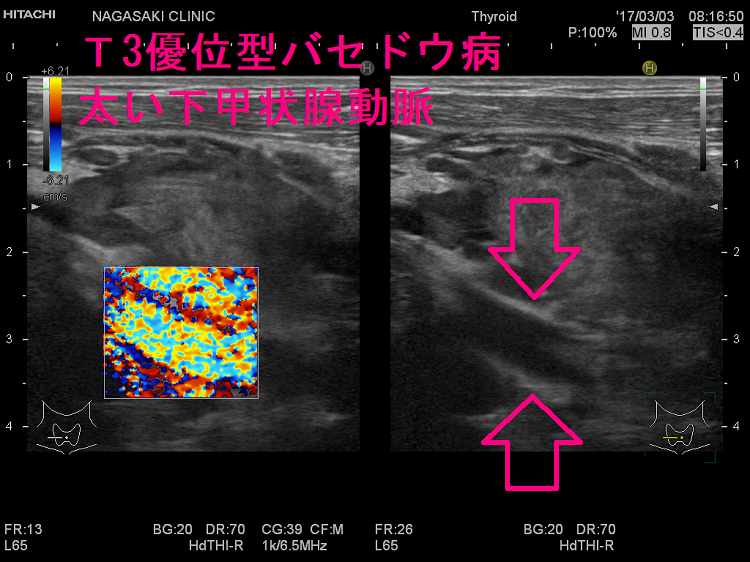

ケース③ 異常に太い下甲状腺動脈

T3優位型バセドウ病の異常に太い下甲状腺動脈。総頚動脈とほぼ同じ太さで、赤・青・黄が混じった乱流になっています。下甲状腺動脈血流速度(ITA-PSV)も異常に高く、186cm/sでした。

難治性T3優位型バセドウ病は若年女性に多く、甲状腺組織の2型脱ヨード酵素(DIO 2)活性が異常に高いため、FT4に比べFT3が著明高値になる。巨大甲状腺腫、TSH レセプター抗体(TRAb)異常高値、甲状腺超音波エコー検査で下甲状腺動脈は異常に太く、下甲状腺動脈血流速度ITA-PSVも異常高値。薬物治療抵抗性で、FT4正常化してもFT3は高値、再発繰り返す。I-131治療は1回で終わらず、甲状腺全摘出手術になる。服薬アドヒアランス不良は患者がメルカゾール・プロパジールを服用しない事。難治性バセドウ病と思って薬を増やしても、甲状腺ホルモンは下がらない。

- 甲状腺超音波(エコー)検査で、下甲状腺動脈が異常に太く、下甲状腺動脈血流速度(ITA-PSV)が異常高値